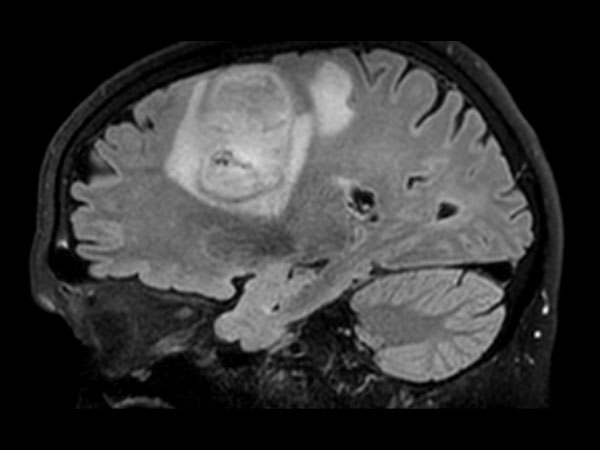

Brain with glioblastoma, incl. 3D APT

Patient with a revasculerized area with small bleedings. Diagnosed as malignant glioblastoom.

3D BrainVIEW FLAIR (sagittal reformat)